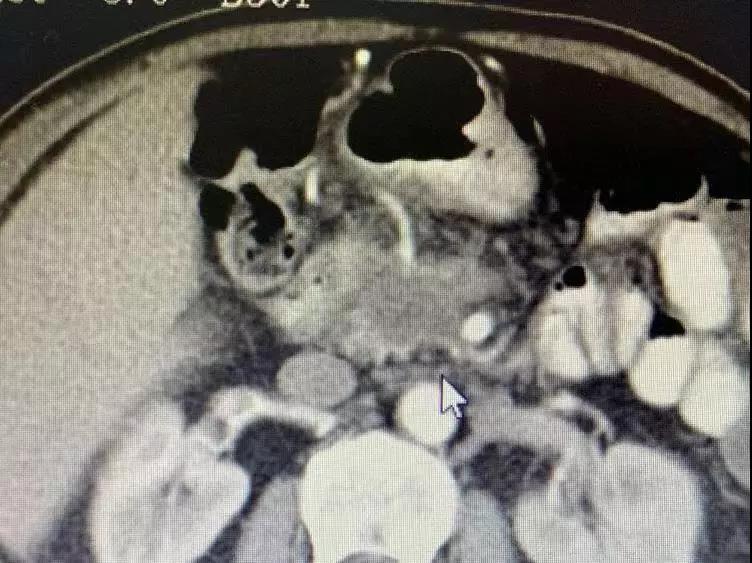

До операции опухоль поджелудочной железы окружает кровеносные сосуды и обнаруживаются метастазы в брюшных лимфатических узлах.

Медсестра сказала мне, что он и его семья были очень добрыми, и они улыбались и кивали вам, когда приветствовали. Было сказано, что он внезапно почувствовал боль в верхней части живота в апреле этого года. Позже в мае он прошел обследование в местной больнице. Неподтвержденная масса в поджелудочной железе размером 3 см была обнаружена вблизи верхней брыжеечной вены, которая предположительно была раком поджелудочной железы. 25 июля у него было еще одно обследование, и его состояние ухудшилось. Опухоль проникла в верхнюю брыжеечную вену и артерию; многочисленные маленькие лимфатические узлы были обнаружены перед полой веной и вблизи аорты. Из-за ограниченных медицинских ресурсов лучшего лечения в Непале не было. Затем его врач порекомендовал ему Онкологическую больницу Фуда.